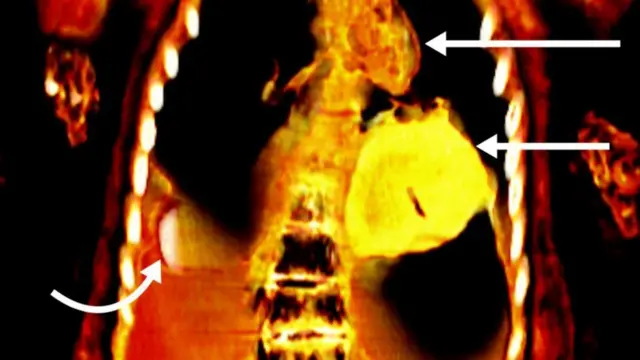

కైరో యూనివర్సిటీకి చెందిన డాక్టర్ సహార్ సలీమ్ బృందం ఈ మమ్మీని సీటీ స్కానర్తో పరిశీలించడంతో లోపల ఏముందో బయటపడింది.

తాయెత్తుల్లాంటి వస్తువులు నలభై తొమ్మిదింటిని ఆ మమ్మీలో గుర్తించారు. వాటిలో చాలా వరకు బంగారంతో చేసినవే.

ఈ మమ్మీలో బాలుడికి నాలుక ఉండాల్సిన చోట బంగారు నాలుక ఉంది. అలాగే గుండె స్థానంలో బంగారంతో చేసిన వస్తువు ఉంది.

అలాగే.. సున్తీ చేయని పురుషాంగాన్ని ఆనుకుని రెండు వేళ్లంత పొడవున్న ఓ వస్తువు ఉంది.